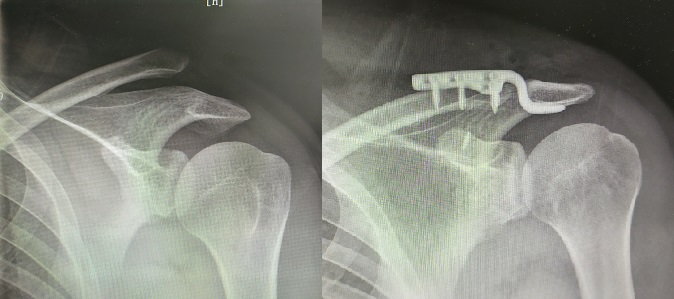

所以人们发明了锁骨钩钢板,现在最主流的固定方式,它既避开了韧带区,又实现了刚性限制下的弹性固定,右图是固定后的X片。

下面附上我年前的一个病例,感兴趣的可以关注我。